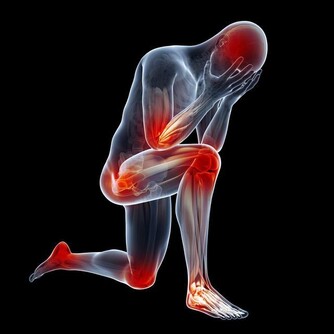

我們知道膝蓋是我身體的一個重要的組成部分,

只有擁有一個健全的完好的膝蓋我們才能夠讓自己活的更加的年輕,

在平時的生活中才能夠步伐更加的強勁有力。

教你如何拯救膝蓋危機

在美國,每年有高達900多萬人去骨科就診,其中大部分都是出於膝蓋的不適。

但不用擔心,如果能稍加註意的話,大多數人根本就不用去醫院。